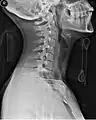

A side view of a person wearing a C spine collar.

A cervical collar, also known as a neck brace, is a medical device used to support and immobilize a person's neck. It is also applied by emergency personnel to those who have had traumatic head or neck injuries,[1] and can be used to treat chronic medical conditions.

Whenever people have a traumatic head or neck injury, they may have a cervical fracture. This makes them at high risk for spinal cord injury, which could be exacerbated by movement of the person and could lead to paralysis or death. A common scenario for this injury would be a person suspected of having whiplash because of a car accident.[2] In order to prevent further injury, such people may have a collar placed by medical professionals until X-rays can be taken to determine if a cervical spine fracture exists.[3] Medical professionals will often use the NEXUS criteria and/or the Canadian C-spine rules to clear a cervical collar and determine the need for imaging. The cervical collar only stabilizes the top seven vertebrae, C1 through C7. (Other immobilizing devices such as a Kendrick Extrication Device or a backboard can be used to stabilize the remainder of the spinal column.[1])